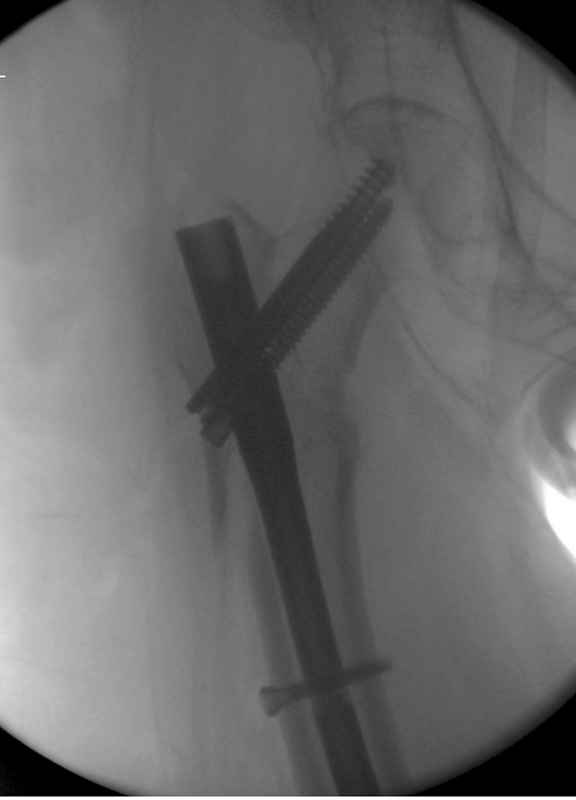

[Ortho] Чрезвертельный перелом бедра

Здесь 83 года, травма в результате падения

Вложение не в текстовом формате было извлечено…

Имя     : #6 IT fx  introp.jpg

Тип     : image/jpeg

Размер  : 22864 байтов

Описание: отсутствует

Url     : http://weborto.net:8080/pipermail/ortho/attachments/20090826/208099a1/attachment-0009.jpg